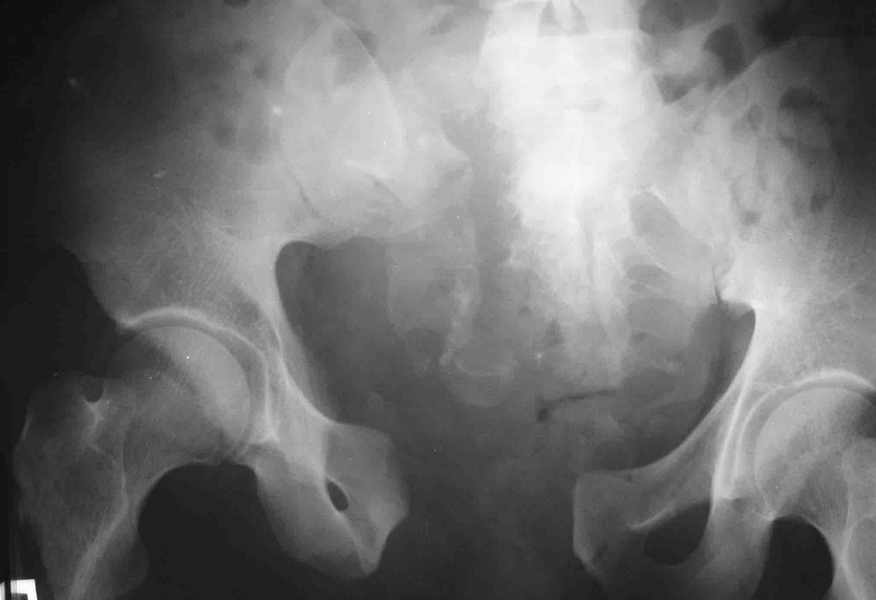

извините за опоздание , вот фотографии

<На R-мме таза ( в прямой проекции, вход и выход из таза) определяется изолированный разрыв лонного сочленения с диастазом 4см,расширение щели правого КПС(вертикальной нестабильности нет, >

Разрыв лонного сочленения с диастазом более 2,5 см говорит о полном разрыве крестцово-подвздошного сочленения (вертикальная нестабильность) или двустороннем характере повреждения (к/п с обеих сторон)

Если повреждение одностороннее - необходима фиксация задних отделов (винт или аппарат)

Если двусторолннее ротационное - можно оставить в передней раме.

Необходимость открытой репозиции и внутренней фиксации определяется площадью ПЛОТНОГО контакта лонных костей, если она меньше 2/3 лучше не ждать

3 месяцев.

Даже если контакт идеальный синтез пластиной

поможет уменьшить риск хр. неестабильности (особенно если пациент тучный, а аппарат ненадежный), быстрее снять аппарат, быстрее активизируется.

В представленном случае повреждение несомненно ротационное и реальный диастаз как раз около пограничных 2,5 см, репозиция идеальная, достигнута в первые дни после травмы. Я бы ограничился 3 мес фиксации в аппарате с ограничением нагрузки первый месяц, и функциональными снимками в 6 -8 недель.